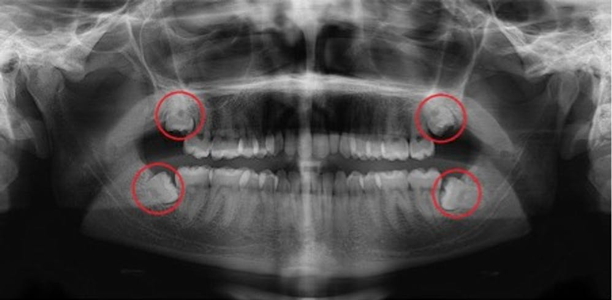

At your initial consultation, your dentist will likely recommend taking a full mouth radiograph known as an Orthopantomograph or an OPG. This radiograph (x-ray) will show the degree and direction of the impaction.

A person generally has four wisdom teeth, one in each corner of the mouth. When all four of the “third molars” develop normally alongside the rest of your teeth and they are perfectly healthy, they are considered an asset to your mouth. However, wisdom teeth usually either fail to erupt into their expected position or they erupt at an awkward angle and become impacted.